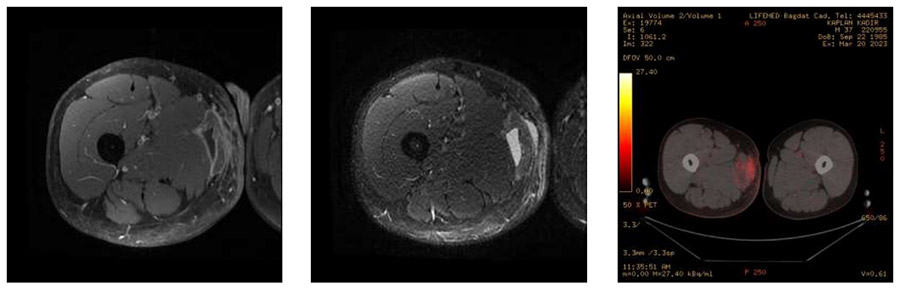

Ameliyat Öncesi: Plansız ameliyat sonrası kalıntı tümör dokusunun MR ve PET-CT görüntüsü